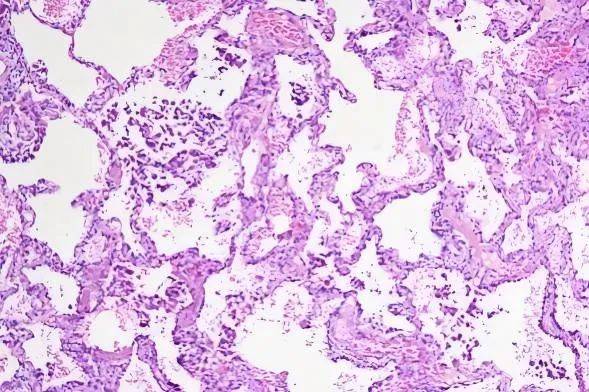

3、从切片到病理诊断:染色与观察

由于白片在显微镜下难以分辨细胞形态,检验人员会先用染色剂处理白片,这个过程叫“苏木精-伊红染色”或“HE染色”,就好比用水彩笔对一张白图进行上色描摹。处理过后,白片上的细胞会带上颜色,称为“HE染色片”。病理医生通过在显微镜下观察HE染色片上的细胞形态、组织结构、肿瘤浸润情况,再结合临床信息,就可以判断肿瘤具体类型、良性恶性、恶性程度等,并出具诊断报告。

从HE染色片到完成病理诊断,一般需要1天的时间,标本量多的时候,病理医生阅片工作量增加,可能需要更长的时间。

肺癌HE染色片在显微镜下的视野(图片来源:内部资料)